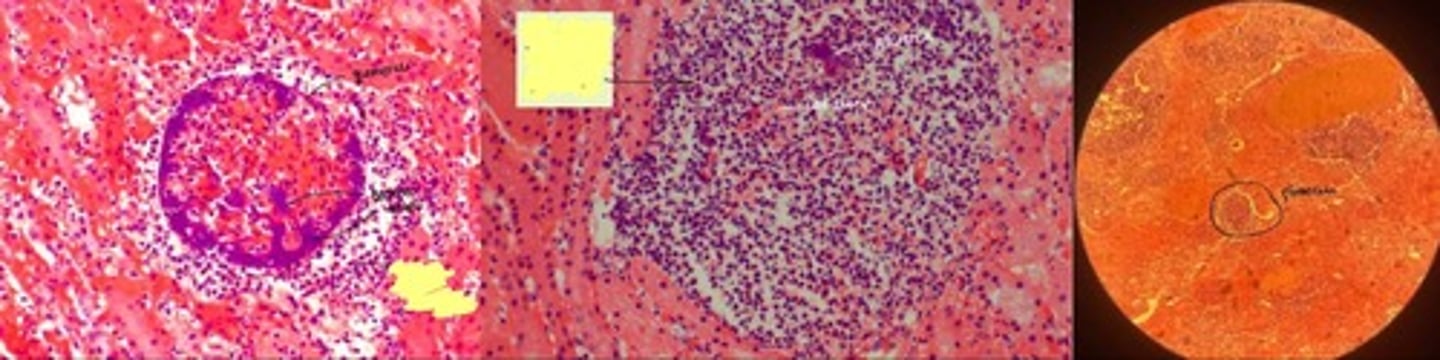

Non-purulent encephalitis

- perivascular cuffing w/ lymphocytes of congested vessel

- increased glial cells => glialosis rosettes

- focal neuronal loss

- increased plasma + macrophages